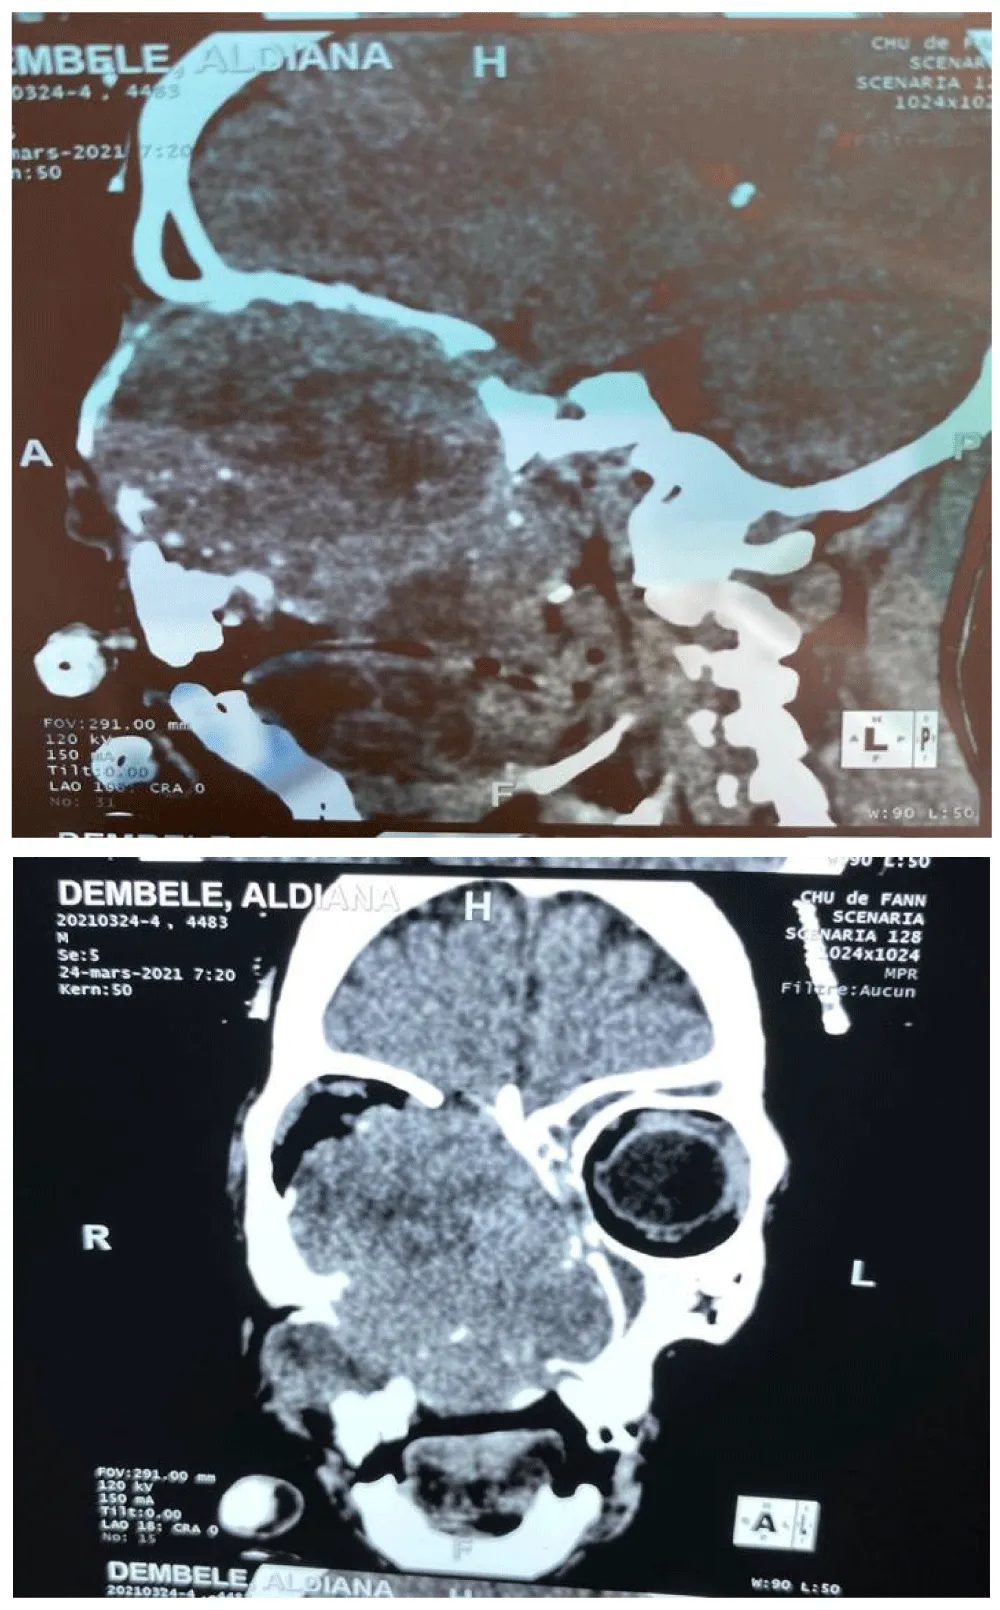

Computed tomography (CT) was performed in 87.3% of patients (n=69) (Figure 4), and two patients underwent MRI, allowing visualization of the tumor and assessment of its locoregional and distant spread. The lesions generally presented as a solid, homogeneous tumor mass, enhancing after contrast injection, often osteolytic, and occupying the maxillary sinus. Data analysis showed that epithelial tumors accounted for 81% of cases and non-epithelial tumors for 19% of cases, of which 50.6% were squamous cell carcinomas and 16.5% were adenocarcinomas.

Regarding histological distribution, the results of this series are consistent with the data in the literature: epithelial tumors predominate [7,12], with a predominance of squamous cell carcinomas, representing 50% of cases, followed by adenoid cystic carcinomas [13,14]. Advanced locoregional spread, confirmed by CT imaging, which is the key diagnostic test, is often present at the time of initial diagnosis, despite a short interval between the onset of the first symptoms and consultation. This rapid progression can be explained by the low specificity and late onset of symptoms in maxillary sinus cancer [4]. This allowed us to classify our patients according to the TNM classification. Consequently, 71% of our patients presented at an advanced stage classified as T4, and 24% were classified as T3 [15]. At the time of diagnosis, 70–80% of maxillary sinus cancers show local extension [16] and are classified as T3 or T4 according to the American Joint Committee on Cancer staging system [17]. Unlike other malignant tumors of the head and neck, where the incidence of cervical lymph node metastasis is high, global data from the literature indicate that lymph node metastases are rare in sinonasal malignancies [2,9]. Our study reported similar findings, with seventy percent of patients being lymph node–negative. Despite the low incidence of cervical lymph node metastasis in maxillary sinus squamous cell carcinoma, which is generally managed conservatively, Scurry et al. reported regional recurrence rates of up to 18% and emphasized the need for elective neck dissection in N0 necks [27].